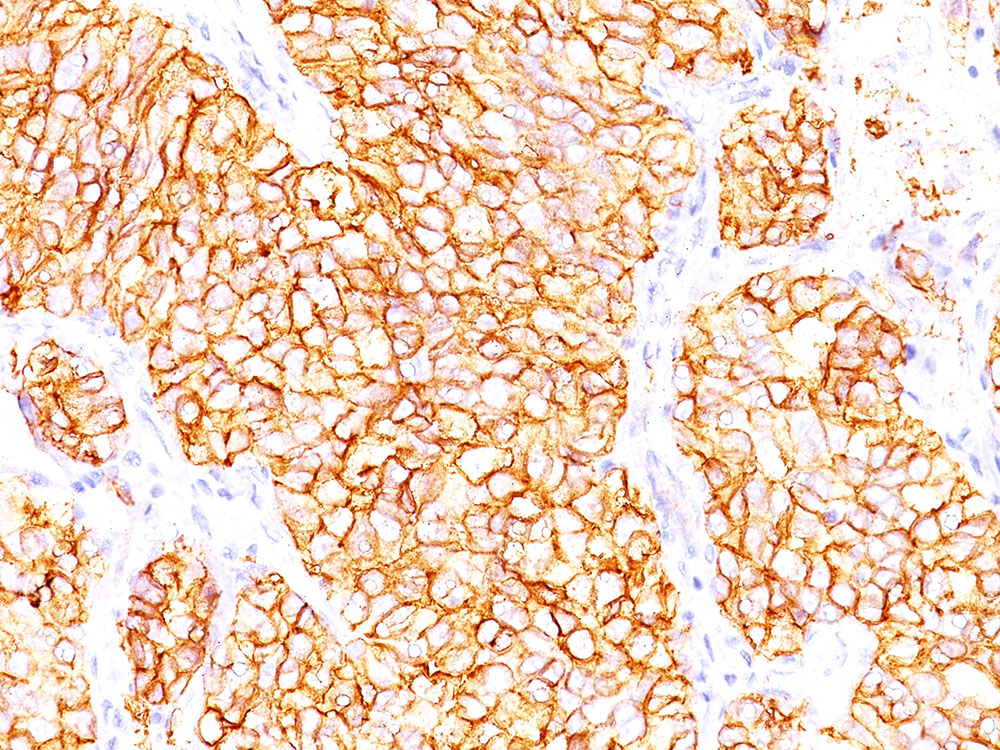

Formalin-paraffin human renal cell carcinoma stained with RCC Ab (66.4.C2). Note cytoplasmic & cell surface staining of tumor cells. |